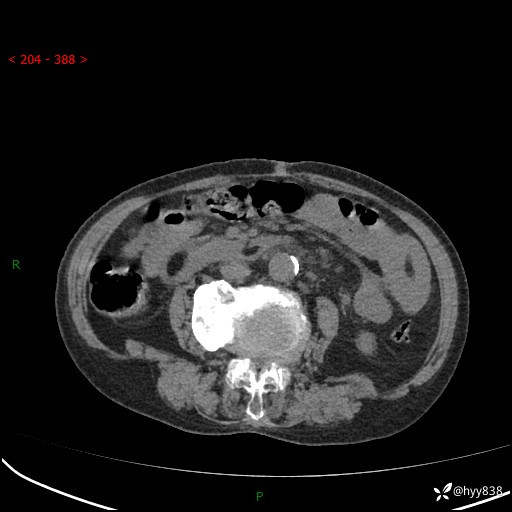

全腹部CT平扫